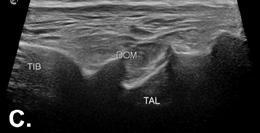

Imagini ecografice la nivelul cotului (A, B) și gleznei (C) cu modificări severe osoase și cartilaginoase, sugestive pentru un stadiu avansat de hemofilie (scor cartilaj 4, scor os 2)